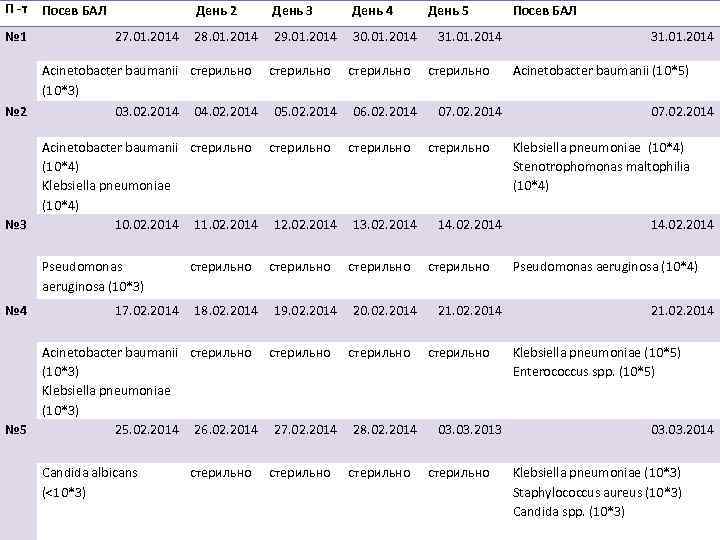

П -т № 1 Посев БАЛ День 2 27. 01. 2014 28. 01. 2014 Acinetobacter baumanii стерильно (10*3) № 2 № 3 03. 02. 2014 № 5 29. 01. 2014 стерильно 05. 02. 2014 День 4 30. 01. 2014 стерильно 06. 02. 2014 День 5 31. 01. 2014 стерильно 07. 02. 2014 Посев БАЛ 31. 01. 2014 Acinetobacter baumanii (10*5) 07. 02. 2014 Acinetobacter baumanii стерильно Klebsiella pneumoniae (10*4) Stenotrophomonas maltophilia Klebsiella pneumoniae (10*4) 10. 02. 2014 11. 02. 2014 12. 02. 2014 13. 02. 2014 14. 02. 2014 Pseudomonas aeruginosa (10*3) № 4 04. 02. 2014 День 3 17. 02. 2014 стерильно 18. 02. 2014 стерильно 19. 02. 2014 стерильно 20. 02. 2014 стерильно 21. 02. 2014 Pseudomonas aeruginosa (10*4) 21. 02. 2014 Acinetobacter baumanii стерильно Klebsiella pneumoniae (10*5) (10*3) Enterococcus spp. (10*5) Klebsiella pneumoniae (10*3) 25. 02. 2014 26. 02. 2014 27. 02. 2014 28. 02. 2014 03. 2013 03. 2014 Candida albicans (<10*3) стерильно Klebsiella pneumoniae (10*3) Staphylococcus aureus (10*3) Candida spp. (10*3)

П -т № 1 Посев БАЛ День 2 27. 01. 2014 28. 01. 2014 Acinetobacter baumanii стерильно (10*3) № 2 № 3 03. 02. 2014 № 5 29. 01. 2014 стерильно 05. 02. 2014 День 4 30. 01. 2014 стерильно 06. 02. 2014 День 5 31. 01. 2014 стерильно 07. 02. 2014 Посев БАЛ 31. 01. 2014 Acinetobacter baumanii (10*5) 07. 02. 2014 Acinetobacter baumanii стерильно Klebsiella pneumoniae (10*4) Stenotrophomonas maltophilia Klebsiella pneumoniae (10*4) 10. 02. 2014 11. 02. 2014 12. 02. 2014 13. 02. 2014 14. 02. 2014 Pseudomonas aeruginosa (10*3) № 4 04. 02. 2014 День 3 17. 02. 2014 стерильно 18. 02. 2014 стерильно 19. 02. 2014 стерильно 20. 02. 2014 стерильно 21. 02. 2014 Pseudomonas aeruginosa (10*4) 21. 02. 2014 Acinetobacter baumanii стерильно Klebsiella pneumoniae (10*5) (10*3) Enterococcus spp. (10*5) Klebsiella pneumoniae (10*3) 25. 02. 2014 26. 02. 2014 27. 02. 2014 28. 02. 2014 03. 2013 03. 2014 Candida albicans (<10*3) стерильно Klebsiella pneumoniae (10*3) Staphylococcus aureus (10*3) Candida spp. (10*3)